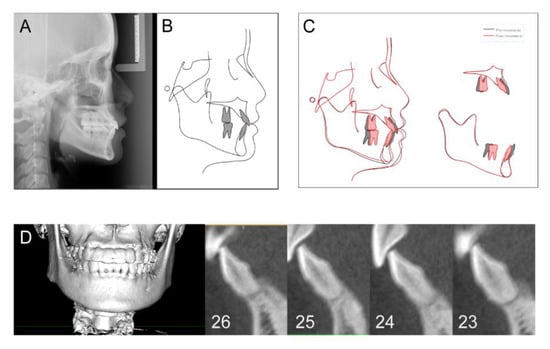

| Tooth | 26 | 25 | 24 | 23 | Mean ± SD |

|---|---|---|---|---|---|

| Lingual (mm2) | 1.49 | 1.74 | 1.82 | 1.09 | 1.54 ± 0.33 |

| Labial (mm2) | 0.68 | 1.86 | 0.68 | 0.94 | 1.04 ± 0.56 |

| Coronal (mm) | 0.40 | 0.63 | 0.30 | 2.11 | 0.86 ± 0.84 |

| Middle (mm) | 1.14 | 0.88 | 0.76 | 2.22 | 1.25 ± 0.67 |

| Apical (mm) | 0.26 | 1.14 | 0.31 | 1.87 | 0.72 ± 0.77 |